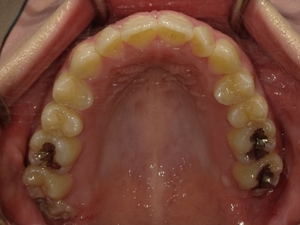

ガタガタとした歯並びや八重歯(叢生)CASE53